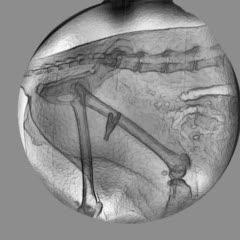

The researchers examined 120 cats and found that 39 were suffering from osteoarthritis. They established an evaluation chart for measuring the cats' pain by looking at their kinetic gait analysis, which reveals impairment in their limbs, their daily activity as recorded by an accelerometer, and how sensitive the cat is to touch by testing what level of force will cause the cat to withdraw its paw.

Scientists at the University of Montreal's Quebec Research Group in Animal Pharmacology have found a way to recognize and treat osteoarthritis in cats -- a condition that the owner might not notice and that can make even petting painful.(Photo Credit: GREPAQ, Université de Montréal)